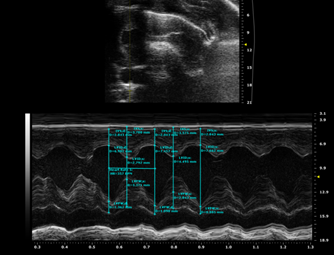

觀察指標:心臟B超檢測 EF及左心室舒張末內(nèi)徑(LVEDD)和左室收縮末內(nèi)徑(LVESD);Masson染色或天狼星紅染色觀察心肌組織纖維化情況,伊文思藍-TTC染色觀察梗死面積;HE染色觀察病理;ELISA檢測血清中的TNF-α、IL-1β及IL-6等炎癥因子。

3573634484425250063-14

圖注:TAC造模前心電圖

圖注:模型前正常SD大鼠B超圖

圖注:TAC模型4周后心電圖